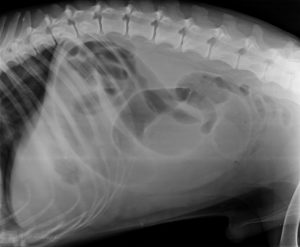

Ovdje objavljujem drugu rtg sliku, ali ne znam da li je to slika rendgena od 13. ili 14. travnja 2021. i da li je to zaista rendgen moga psa jer nema nigdje moga imena ili imena moga psa. Nakon toliko dana, taj nalaz može biti podmetnut i ne mora biti slika moga psa.